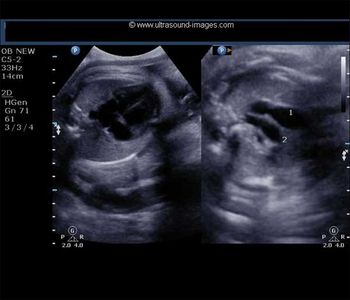

Excessive traction blamed for brachial plexus injury; bowel injury after laparoscopy; prolonged second stage blamed for CP; failure to perform timely cesarean blamed for child’s developmental delay; uterus perforated during hysteroscopy; severe IUGR not detected in high-risk pregnancy